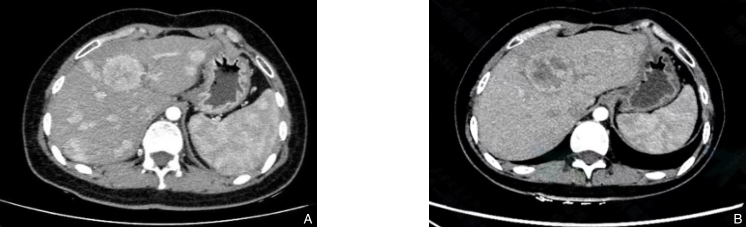

图1 患者1上腹部增强CT图像 A:2021年9月8日结果;B:2022年5月3日结果Fig.1